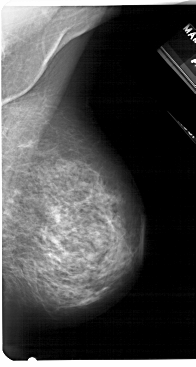

A_1279_1.LEFT_CC

LEFT_CC LINES 5146 PIXELS_PER_LINE 2731 BITS_PER_PIXEL 12 RESOLUTION 43.5 OVERLAY